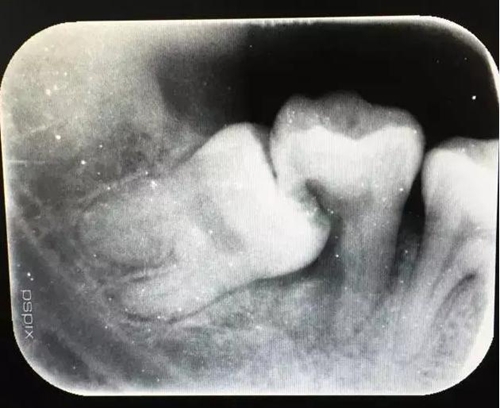

圖1.術前的CBCT檢查:37頰側部分牙根被完全壓迫吸收。

圖2.術前的x線根尖片影像檢查:47遠中牙根吸收。

11.jpg